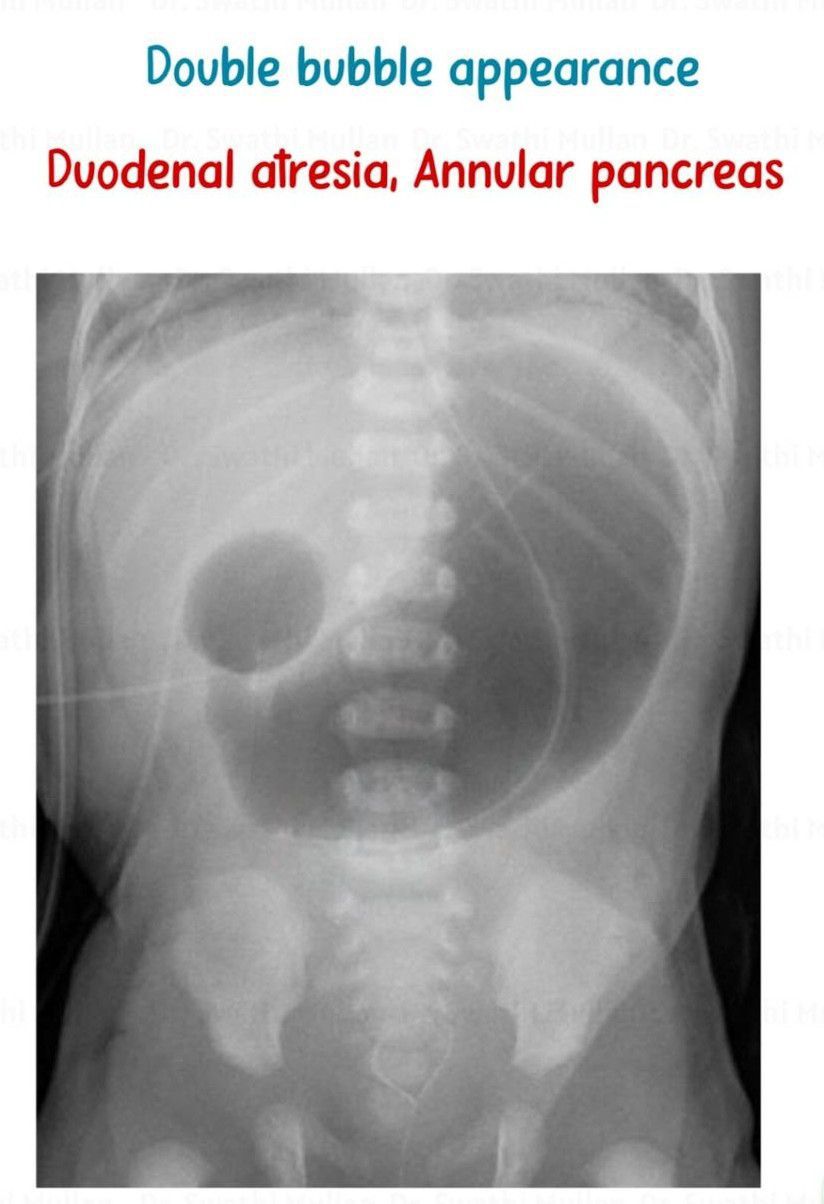

Double Bubble Appearance

Can you name the conditions in which this appearance is seen?